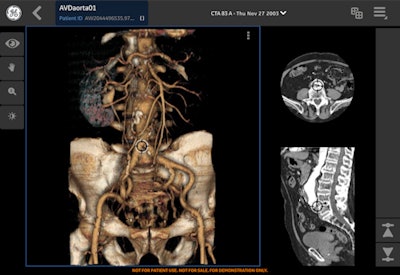

GE Healthcare is promoting cloud-based technologies for storing and distributing the data previously held on departmental systems. At ECR 2016, it is highlighting the next stage in this process with the GE Health Cloud, which is described as a new cloud ecosystem with applications for connecting radiologists and clinicians and helping to facilitate collaboration across care pathways and multidisciplinary teams.

Four new applications include an advanced visualization app for managing image postprocessing and allowing radiologists and clinicians to view advanced 3D images anytime, anywhere. There is also a virtual meeting app to help multidisciplinary teams in their collaborative care planning and reducing preparation time for such meetings by up to 20%. The company is also presenting a case exchange app allowing affiliated and nonaffiliated users to share images and reports and to confer quickly on patient cases and treatment plans. Finally, there is an image access portal for distributing longitudinal patient imaging data, offering potential improvements in turnaround times for patient reports.